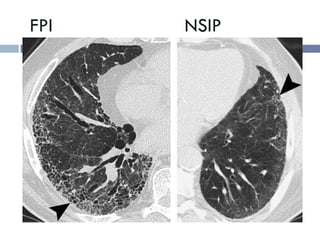

FPI NSIP

• #25 Comparison of high-resolution CT features between UIP and NSIP. (a) UIP is characterized by heterogeneous lung abnormalities consisting of subpleural honeycombing (arrowhead), reticular opacities, and traction bronchiectasis. (b) NSIP demonstrates homogeneous lung involvement with predominance of ground-glass opacity combined with subpleural linear opacities and micronodules. The microcysts in NSIP (arrowhead) are much smaller than the honeycombing in UIP.